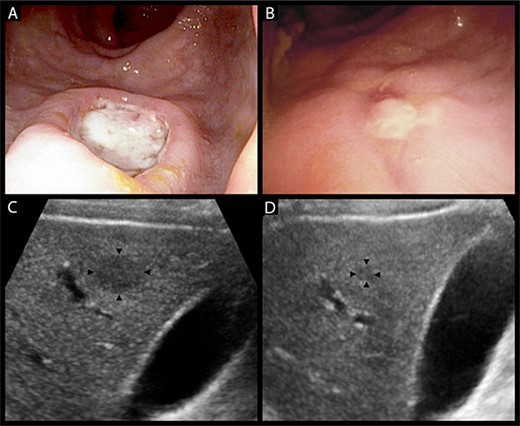

An inpatient colonoscopy demonstrated a 2-cm ulcer with heaped margins and a necrotic base in the lower rectum that was biopsied with endoscopic forceps (Fig. 2A). A liver ultrasound was performed for further characterization of the liver lesions (Fig. 2C). The patient was discharged with resolution of his acute symptoms, for ongoing close follow-up as an outpatient. Histopathology of the rectal lesion returned as ulceration with chronic inflammation and atypical crypt epithelium, with no evident neoplastic change on immunostaining. An early interval elective colonoscopy was attended at which time the rectal ulcer had almost entirely resolved (Fig. 2B). Concurrent gastroscopy at this time was unremarkable. The patient was referred for a CT-guided liver biopsy, with a finding of scattered granulomas with extensive areas of necrosis. There were no observed neoplastic cells or microorganisms.

(A) heaped ulcer with a necrotic base in the lower rectum seen on colonoscopy, representing a syphilitic chancre. (B) The same lesion resolving on interval colonoscopy 4 weeks later, prior to the commencement of treatment for syphilis. (C) Hypoechoic liver lesion in segment 6 measuring 19 by 14 mm. (D) The same lesion has decreased to 6 by 5 mm at 6 weeks post-treatment.

The case was discussed with the patient’s HIV physician who informed the team of the patient’s history of multiple episodes of syphilis infection. Following this, serological assessment with the rapid plasma reagin test returned a titre of 1:32, increased from a previous result of 1:16, confirming syphilis reinfection. The gross and histological appearances of the rectal lesion were considered consistent with a syphilitic chancre, with the liver lesions presumed to be visceral gummata—granulomatous lesions of tertiary syphilis. The patient was commenced on a three-dose course of intramuscular benzathine penicillin G. A repeat liver ultrasound at 6 weeks post-treatment demonstrated a significant reduction in the size of a dominant lesion in the right anterior liver section, with no other appreciable lesions (Fig. 2D). The patient awaits repeat syphilis serological testing and surveillance liver ultrasound to confirm complete clearance.